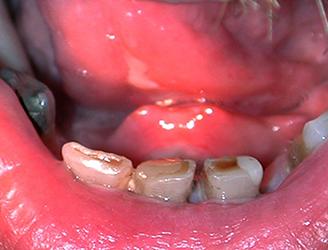

Papilloomavirusinfektion oireet vaihtelevat. Suun limakalvoilla voi esiintyä sekä iholle että sukuelinten limakalvoille syyliä aiheuttavia virustyyppejä. Kondylooma voi olla piilevänä täysin oireeton. Se voi myös näkyä suun limakalvoilla kukkakaalimaisina, sileä- tai rosopintaisina, alustastaan koholla olevina muutoksina.

Jos kuppaa ei hoideta, tauti siirtyy piilevään vaiheeseen, kunnes se muutaman kuukauden kuluttua tartunnasta aktivoituu uudelleen. Tässä ns. toisen vaiheen kupassa oireita ei välttämättä aina ole tai ne voivat olla hyvin moninaisia. Suun limakalvoille voi ilmaantua esimerkiksi vaaleita läikkiä (kuvassa alla). Jos tauti jää edelleen hoitamatta, oireet häviävät, ja tauti muuttuu piileväksi jopa vuosikymmenten ajaksi. Kuppa voi kuitenkin myöhemmin taas aktivoitua ja aiheuttaa mm. vakavia hermostovaurioita.